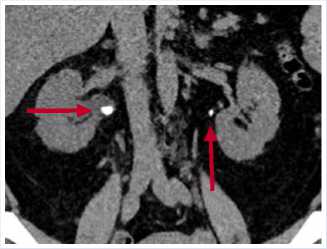

Рис. 1. МСКТ в нативном режиме, сделанная в марте 2023 г. Стрелками указаны конкремент ЛМС справа (с наличием расширения ЧЛС) и ЛМС слева.

10,9 ммоль/л, креатинин 124 мкмоль/л, мочевая кислота 445 мкмоль/л, пациентке рекомендовано выполнение анализа суточной мочи и низкодозная КТ органов мочевыделительной системы в нативном режиме. Диагностирована выраженная гиперурикурия до 870 мг, по данным КТ выявлено: Чашечно-лоханочная система (ЧЛС) справа расширена: чашечки до 17 мм, лоханка до 44 x 16 мм, в нижней группе чашечек правой почки определяются три конкремента, размерами до 4 мм, плотностью до 420 HU, в лоханке правой почки определяется крупный конкремент, размерами до 15 x 9,5 мм плотностью до 550 HU, мочеточник справа при нативном исследовании без значимого расширения, конкрементов в нем достоверно определяется. Вместе с тем, отмечается уплотнение клетчатки на уровне ЛМС справа, а также по ходу верхней трети мочеточника, где визуализируются лимфатические узлы, расположенные парааортально, максимальными размерами до 19 x 7 мм. ЧАС левой почки не расширена. Однако, отмечается наличие мелкого конкремента в области лоханочно-мочеточникового перехода, размерами до 4,8 x 3,5 мм, плотностью до 351 HU (Рис. 1, 2). Предложена госпитализация для проведения оперативного вмешательства по срочным показаниям с целью дренирования правой почки, от чего пациентка отказалась. Учитывая данные суточного анализа мочи, наличие конкрементов верхних мочевых путей (ВМП) относительно низкой плотности, заподозрен мочекислый (уратный) нефролитиаз. От проведения литолитической терапии в амбулаторных условиях пациентка также отказалась.